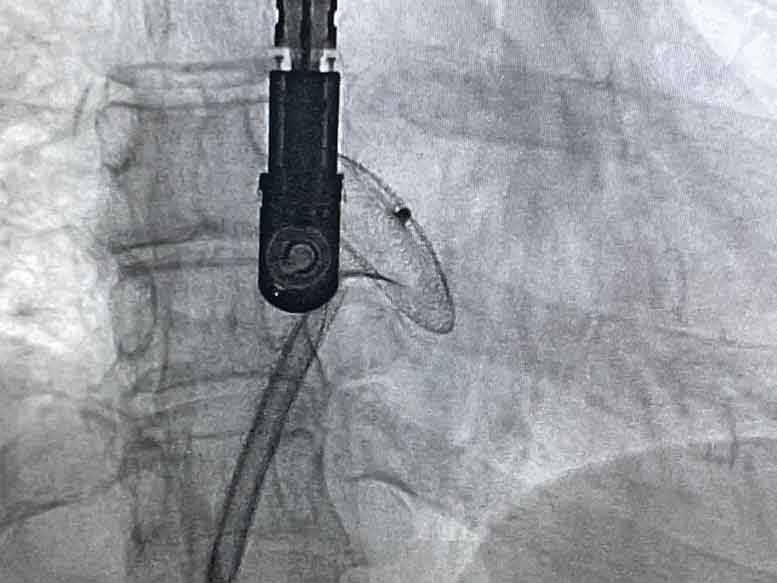

Уперше на Волині у Ковельському МТМО провели ендоваскулярну операцію із закриття множинних дефектів міжпередсердної перетинки. Вроджену ваду серця 40-річній пацієнтці (мамі 4-х дітей!) діагностували зовсім недавно.

Вона скаржилась на швидку втомлюваність та задишку. Хвора пройшла обстеження на базі кардіохірургічного центру медичного об’єднання. Результат ультразвукового дослідження серця, який здійснила лікар-кардіолог Ольга Танська, підтвердив наявність у жінки вродженої патології, про яку вона навіть не підозрювала.

Операція пройшла успішно, пацієнтку перевели у палату інтенсивної терапії, де вона перебуватиме під наглядом лікарів ще декілька днів.